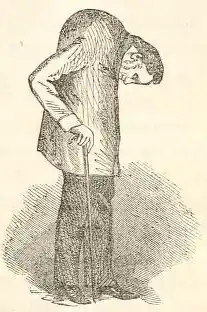

Gait

The hunched position that often results from complete spinal fusion can have an effect on a person's gait. Increased spinal kyphosis will lead to a forward and downward shift in center of mass (COM). This shift in COM has been shown to be compensated by increased knee flexion and ankle dorsiflexion. The gait of someone with ankylosing spondylitis often has a cautious pattern because they have decreased ability to absorb shock, and they cannot see the horizon.[54]

In 1858, David Tucker published a small booklet which clearly described the case of Leonard Trask, who had severe spinal deformity subsequent to AS.[65] In 1833, Trask fell from a horse, exacerbating the condition and resulting in severe deformity. Tucker reported:

It was not until he [Trask] had exercised for some time that he could perform any labor ... [H]is neck and back have continued to curve drawing his head downward on his breast.

The account of Trask became the first documented case of AS in the United States, owing to its indisputable description of inflammatory disease characteristics of AS and the hallmark of deforming injury in AS.